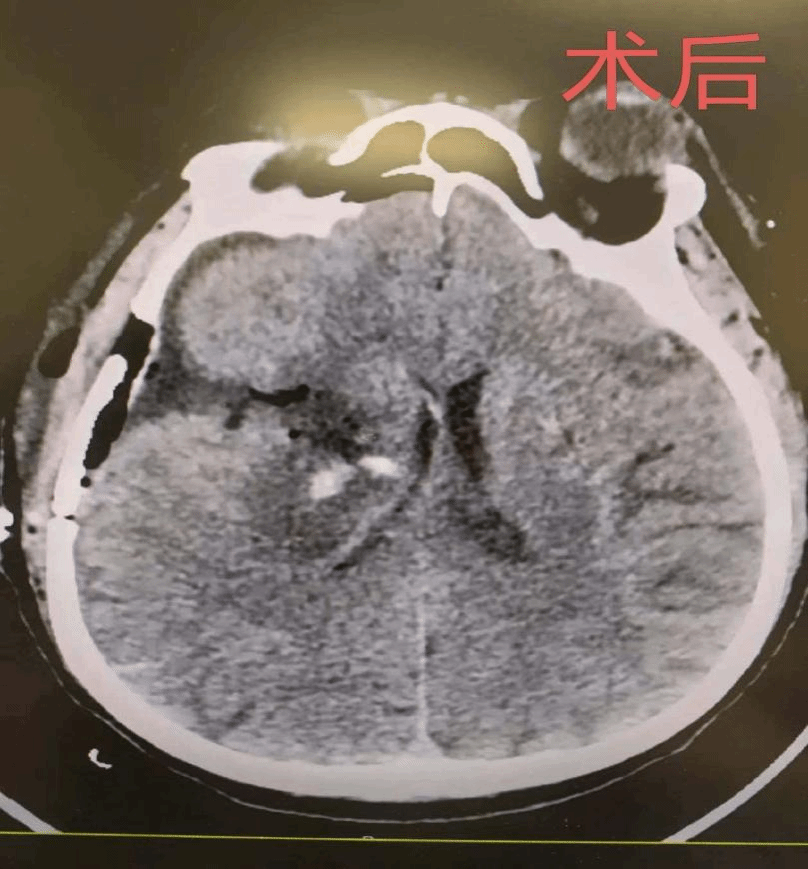

手术过程顺利,术后复查头颅CT显示,颅内血肿已基本清除,颅内压有效降低,为患者神经功能恢复创造了良好条件。